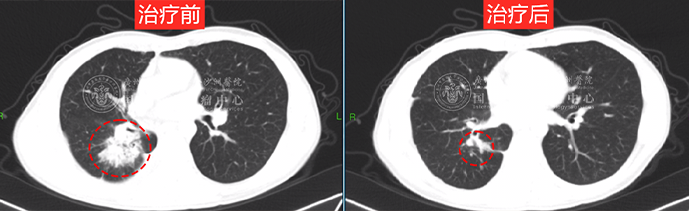

经过1个周期的精准放疗后,徐女士影像复查肿瘤有了明显缩小,病情也得到了很好的控制,咳嗽、疼痛、胸闷气短等情况都得到明显改善。徐女士也开始做一些低强度的运动煅炼,不会觉得憋气不适,完全不影响正常的肺部功能。

瘤体明显缩小 效果显著